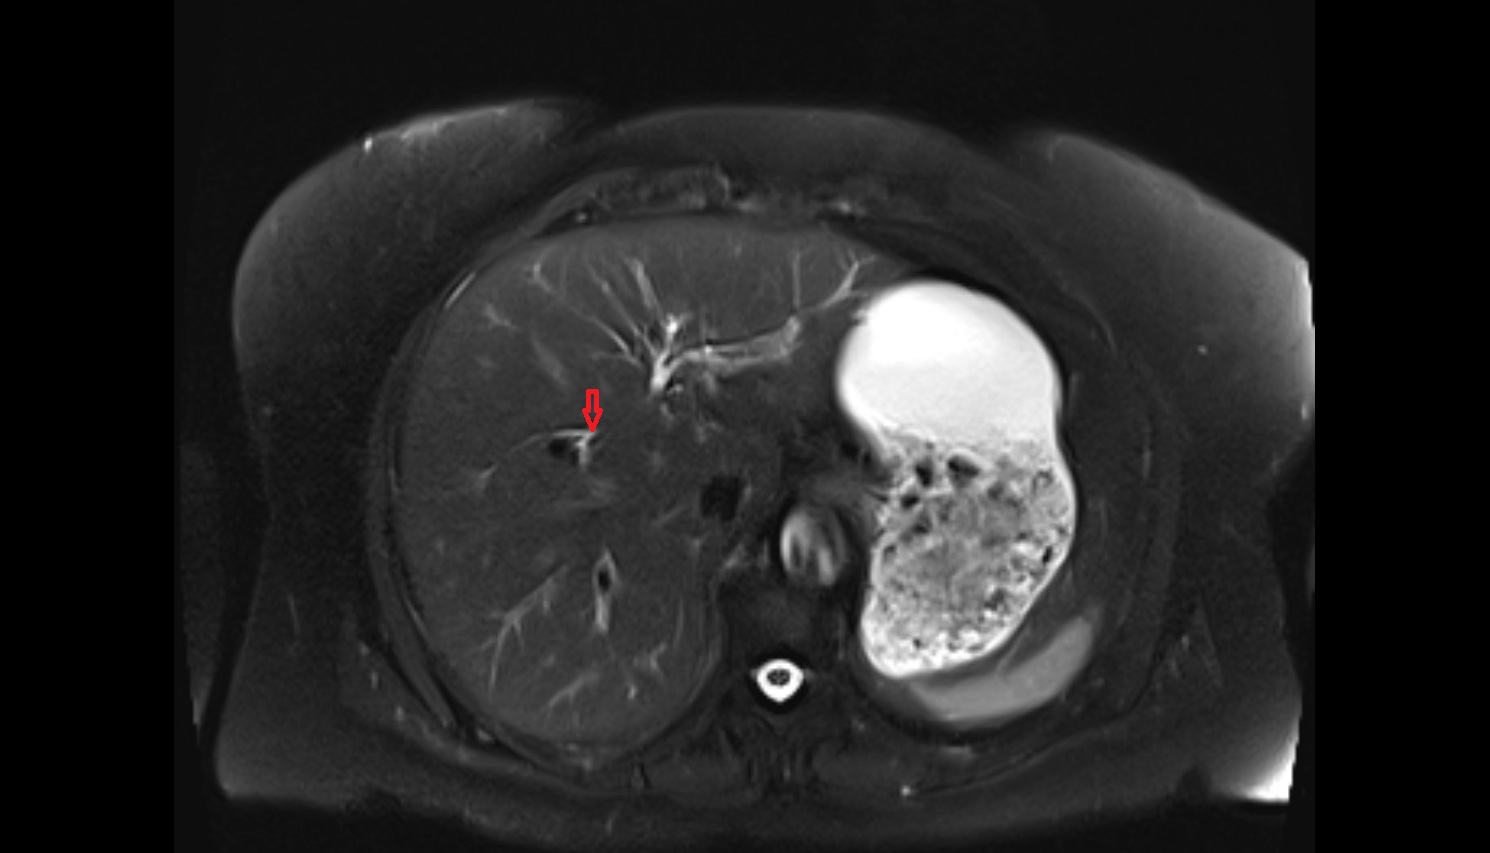

- Left lobe of liver

- Right lobe of liver

- Liver

- Liver Segment I – Caudate lobe

- Liver Segment II – Left lateral superior segment

- Liver Segment III – Left lateral inferior segment

- Liver Segment IVa – Left medial superior segment

- Liver Segment IVb – Left medial inferior segment

- Liver Segment V – Right anteroinferior segment

- Liver Segment VI – Right posteroinferior segment

- Liver Segment VII – Right posterosuperior segment

- Liver Segment VIII – Right anterosuperior segment